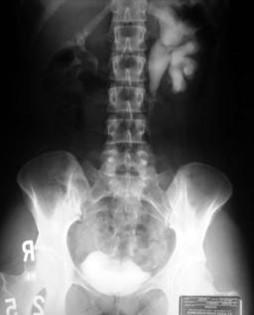

Urinary Tract Obstruction in Polycystic Renal Disease1 Diagnostic Radiology Zoran L. Barbaric, M.D., Robert F. Spataro, M.D., and Arthur J. Segal, M.D. Neoplasm Unknown Infundibular obstruction Calculus Unknown Total 7 1 6-17--Fig. 1. ... Visit Document